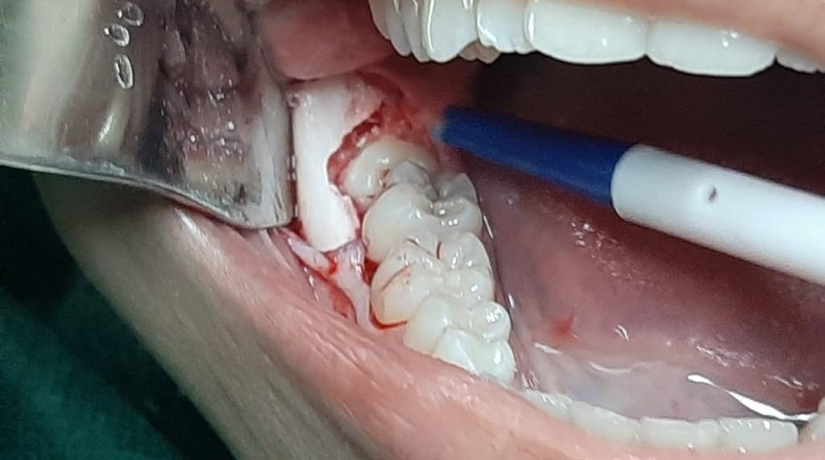

Cirurgia Oral Menor

O Curso em questão é dirigido para o aprendizado da cirurgia oral menor. Por meio de seus objetivos, o curso  visa proporcionar aos alunos atualização dos conhecimentos teóricos e maior treinamento prático sobre os aspectos relacionados à pequenas cirurgias.

• Planejamento e Técnicas Cirúrgicas